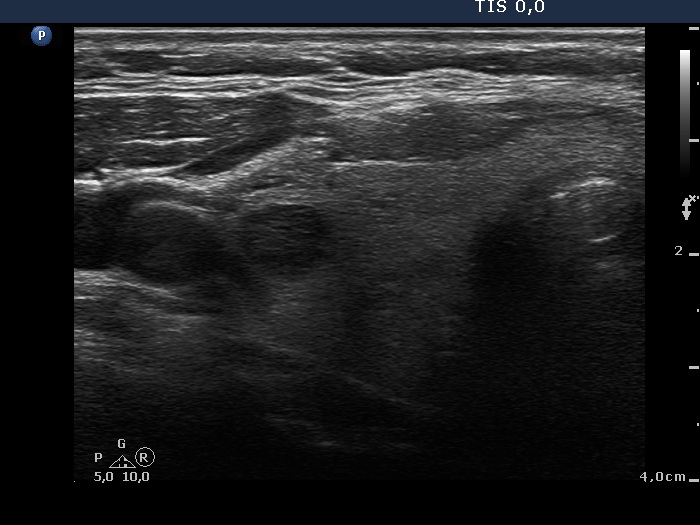

Ultrasonography. The thyroid was echonormal. There were several small discrete partly echonormal, partly moderately hypoechogenic-cystic lesions in the right lobe. The left lobe presented a large nodule composed of peripheral echonormal solid part and a central complex moderately hypoechogenic-cystic area. The hypoechogenic part had a partly chaotic, increased vascular pattern.